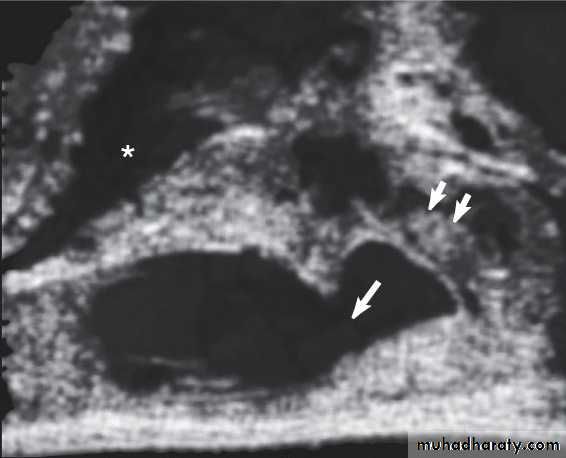

3.Transrectal U.S.(T.R.U.S.)

To assess the prostate,seminal vesicles,ejaculatory duct &vas.Indicated in azospermia with suspected ejaculatory duct obstruction.

Equivocal TRUS findings in suspected ejaculatory duct obstruction can be confirmed by seminal vesicle aspiration.